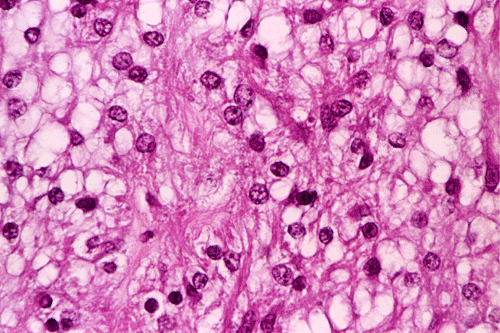

These photos were obtained from the formalin fixed paraffin embedded sections.